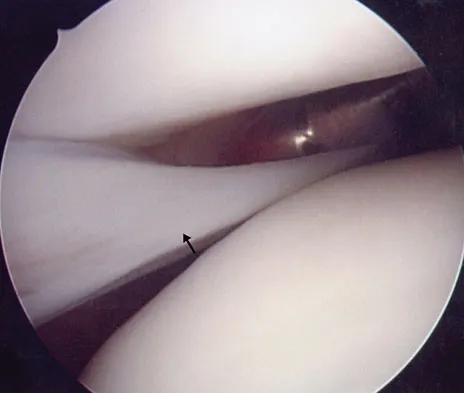

What neurovascular structure is in closest proximity to the probe in the arthroscopic view of the elbow shown in Figure 50?

Correct Answer: Radial nerve

The image shows a view of the radiocapitellar joint from an anterior medial portal. The radial nerve lies on the elbow capsule at the midportion of the capitellum. It is at risk for injury when capsular excision is performed in this region. Field LD, Altchek DW, Warren RF, et al: Arthroscopic anatomy of the lateral elbow: A comparison of three portals. Arthroscopy 1994;10:602-607.